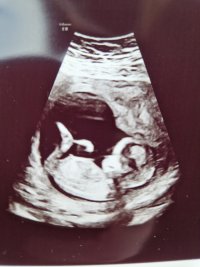

12+0 i dag!